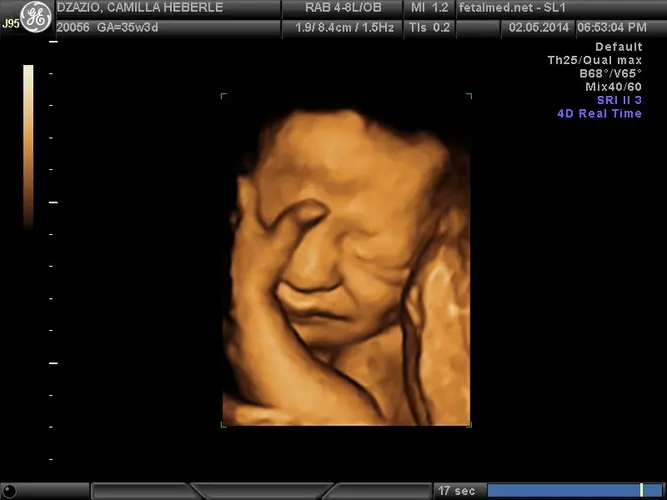

Seu bebê alcançou um marco importante na 35ª semana: agora tem mais de 90% de chances de sobreviver caso nasça prematuramente. Os sistemas vitais estão quase completamente desenvolvidos e maduros, representando um grande avanço em relação às semanas anteriores. Com aproximadamente 45 centímetros de altura e pesando cerca de 2,4 quilos, ele continua ganhando peso significativo – cerca de 230 gramas por semana.

O desenvolvimento cerebral continua em ritmo acelerado, com a formação de novas células cerebrais acontecendo constantemente. Isso faz com que a cabeça ainda pareça um pouco desproporcional em relação ao corpo. O espaço no útero está ficando mais restrito, limitando os movimentos amplos que você sentia nas semanas anteriores. A maioria dos bebês nesta fase já está posicionada com a cabeça para baixo, preparando-se para o parto.

A placenta agora representa aproximadamente um sexto do peso fetal total, continuando seu papel fundamental no suporte nutricional e respiratório do bebê. Nos exames de ultrassom desta semana, pode ser mais desafiador visualizar todas as estruturas do bebê devido ao espaço reduzido e à calcificação óssea avançada, que pode causar sombras acústicas nas imagens.